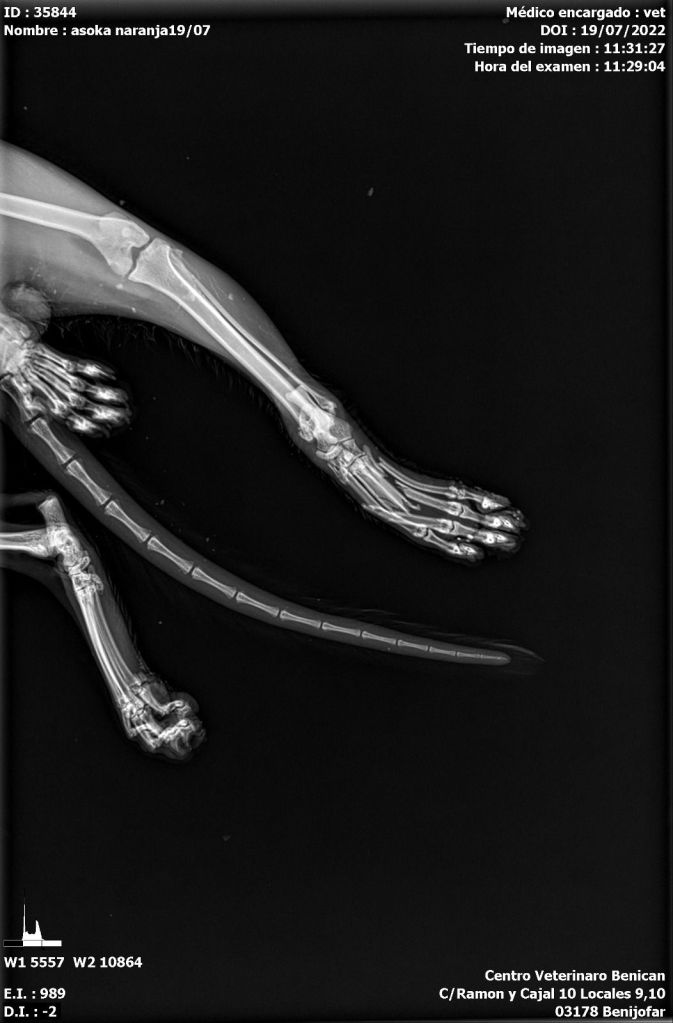

Unser Iker ist schon ein armes Kerlchen. In Spanien wurde er schwer verletzt auf der Straße gefunden. Er hatte einen Autounfall und der Fahrer ließ ihn einfach liegen. Glücklicherweise fand ihn ein lieber Mensch und brachte ihn umgehend zu einem Tierarzt. Sofort wurde er tierärztlich versorgt und geröntgt (s. Röntgenbilder und ein Bild von Iker nach OP). Er hatte einen gebrochenen Schwanz, ein gebrochenes Schienbein, und der Mittelfußknochen des linken Beines war ebenfalls gebrochen. Iker wurde operiert. Die Beinfrakturen wurden mit Nägeln stabilisiert. Der Schwanz musste leider komplett amputiert werden.